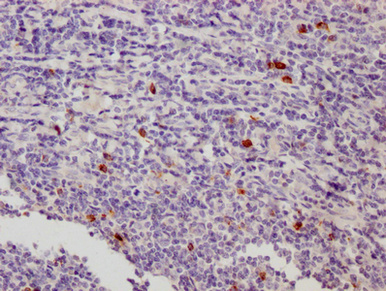

IHC image of CSB-MA012719A0m diluted at 1:500 and staining in paraffin-embedded human appendix tissue performed on a Leica BondTM system. After dewaxing and hydration, antigen retrieval was mediated by high pressure in a citrate buffer (pH 6.0). Section was blocked with 10% normal goat serum 30min at 37°C Then primary antibody (1% BSA) was incubated at 4°C overnight. The primary is detected by a Goat anti-Mouse IgG labeled by HRP and visualized using 0.05% DAB.